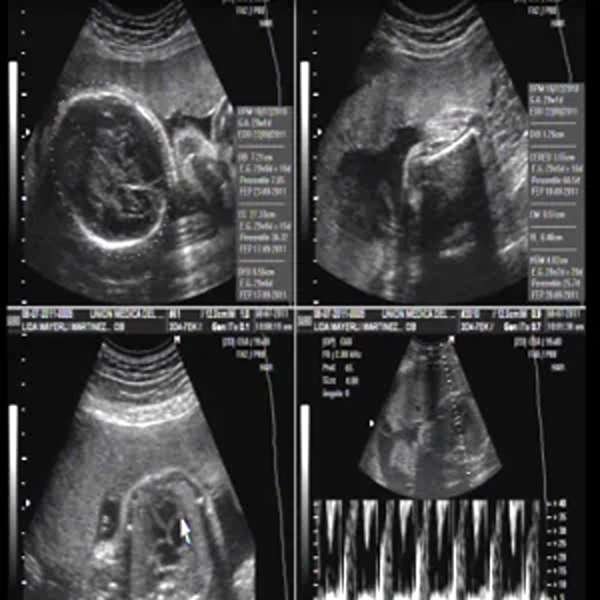

Ecografía Obstétrica Doppler

La ecografía obstétrica Doppler es un estudio avanzado que, además de visualizar el desarrollo del feto, evalúa el flujo sanguíneo en la placenta, el cordón umbilical y otras estructuras maternas y fetales. Es fundamental para detectar problemas en la circulación que puedan afectar el crecimiento del bebé, como insuficiencia placentaria o preeclampsia. Se usa especialmente en embarazos de alto riesgo para garantizar un adecuado suministro de oxígeno y nutrientes. Es un procedimiento seguro, indoloro y clave para el seguimiento prenatal en casos donde se requiera un control más detallado.